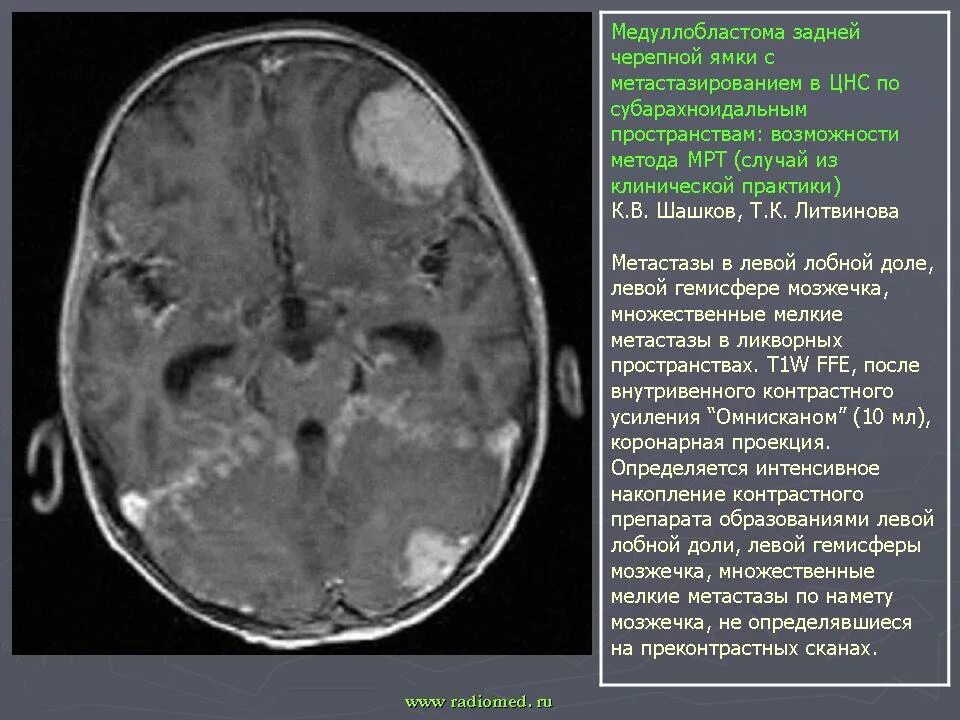

Медуллобластома это